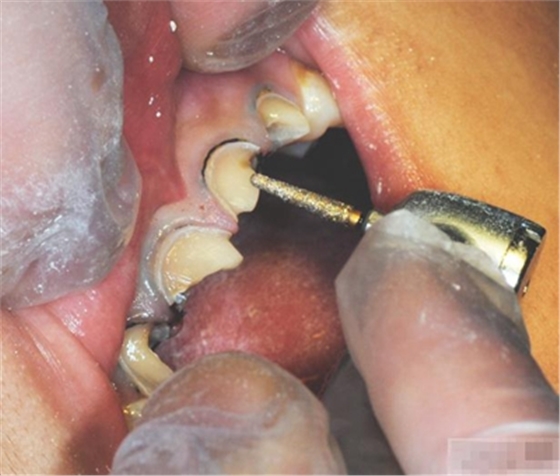

選擇合適的完成鉆制備根管,

通常深入到根管的1/2至2/3處

何種情況應(yīng)該使用纖維樁呢?

是否使用根管纖維樁取決于剩余牙體組織的強(qiáng)度,這主要決定于剩余邊緣嵴的數(shù)量。

a 兩側(cè)邊緣嵴均完整,無需使用根管纖維樁。

b 一側(cè)邊緣嵴缺如:評(píng)估牙體缺損情況??沽π陀幸蓱]則加用根管纖維樁。

c 兩側(cè)邊緣嵴均缺如,必須使用根管纖維樁。

在使用根管纖維樁時(shí)根管預(yù)備的深度應(yīng)該是多少呢?

在回答這個(gè)問題前,首先應(yīng)該了解根管內(nèi)的粘接狀況。最佳的粘接效果發(fā)生于根管的冠1/3和中1/3。由于根1/3的牙本質(zhì)小管往往不能充分敞開,此區(qū)域幾乎沒有粘接作用發(fā)生,所以,根管纖維樁放置的深度無需超過根中1/3。同樣重要的是,根管預(yù)備時(shí)鉆的速度不要過快,防止飛濺的牙膠粘在根管內(nèi)壁上。所以,根管壁的清理也很重要,以確保牙本質(zhì)小管充分開放。Dr.Vanini使用噴砂和酸蝕來充分清理根管壁和窩洞。研究顯示,粘接劑的作用也很重要,粘接根管纖維樁要求使用滲透力強(qiáng)粘結(jié)作用好的粘接劑。